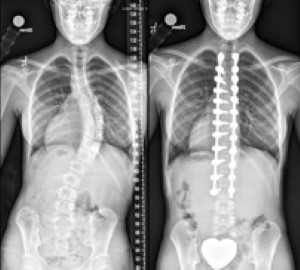

Jessie's spine before and after surgery